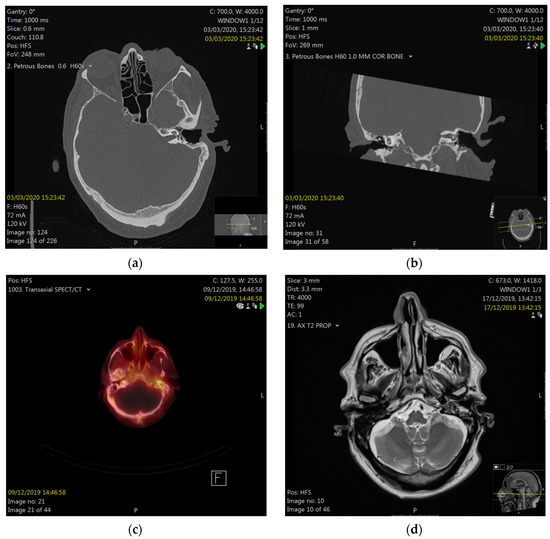

The following work-up included microbiology from the ear, which revealed no bacterial growth, but some Candida species. A tissue biopsy from the ear canal reported hyperkeratosis, without significant inflammation, fungal organisms, dysplasia, or malignancy. His pure-tone audiogram revealed severe-to-profound pantonal hearing loss on the left (85–110 dB) and presbycusis (10–70 dB) on the right. He then underwent computed tomography (CT) scanning of his petrous bones and neck, reporting non-specific soft tissue in the mastoid cavity, post-surgical changes after previous CWD mastoidectomy, with removal of the ossicular chain, and patchy bony erosion of the external ear canal floor, as well as fatty changes in the left parotid gland, as compared to the right. There were normal appearances of the inner ear structures and the right temporal bone, and there was no evidence of local tumor recurrence or metastatic disease. A technetium uptake scan reported increased osteoblastic activity around the bony portion of the left external auditory canal. Magnetic resonance imaging (MRI) showed enhancement of the left facial nerve and small traces of diffusion in isointense/hyperintense material that was present, which involved the operated left mastoid cavity along the roof, floor, and medial aspect (Figure 3).

Facial nerve palsy was the critical symptom in our case, initiating the described comprehensive diagnostic procedure, which was needed to finally reach the correct diagnosis. For acute lower facial nerve palsies, there is no international standard for the optimal extend of diagnostics. However, for ENT specialists, a thorough clinical examination of the ear and parotid gland should be mandatory. Furthermore, the degree of facial nerve impairment should be recorded, which, in clinical routine, is often conducted using subjective measures, such as the House–Brackmann Scale or the Sunnybrook Facial Grading Scale, as objective means, like automated image analysis tools, are still being developed. Electromyography in this context can be helpful in delineating the degree of facial nerve injury and in monitoring the condition. CT scanning of the temporal bone as initial imaging provided, in our case, important information about the regional bony anatomy and extent of disease. Nuclear medicine uptake scans, often used to monitor the treatment response for malignant otitis externa, can provide information about acute inflammation via the accumulation of tracers in the inflamed area. Finally, MRI scanning was rather unspecific for ORNTB, but was helpful in this case to exclude other causes of non-recovering facial nerve palsy.

Figure 3. Computed tomography (CT) of petrous bones in axial (a) and coronal (b) planes, showing a situation after the left canal wall-down mastoidectomy, with patchy bony erosion of the floor of the external auditory meatus (white arrow) and uncovered facial nerve. Nuclear medicine scan (c) showing uptake around the left EAM. Magnetic resonance imaging (MRI) showing enhancement of the left mastoid (d).